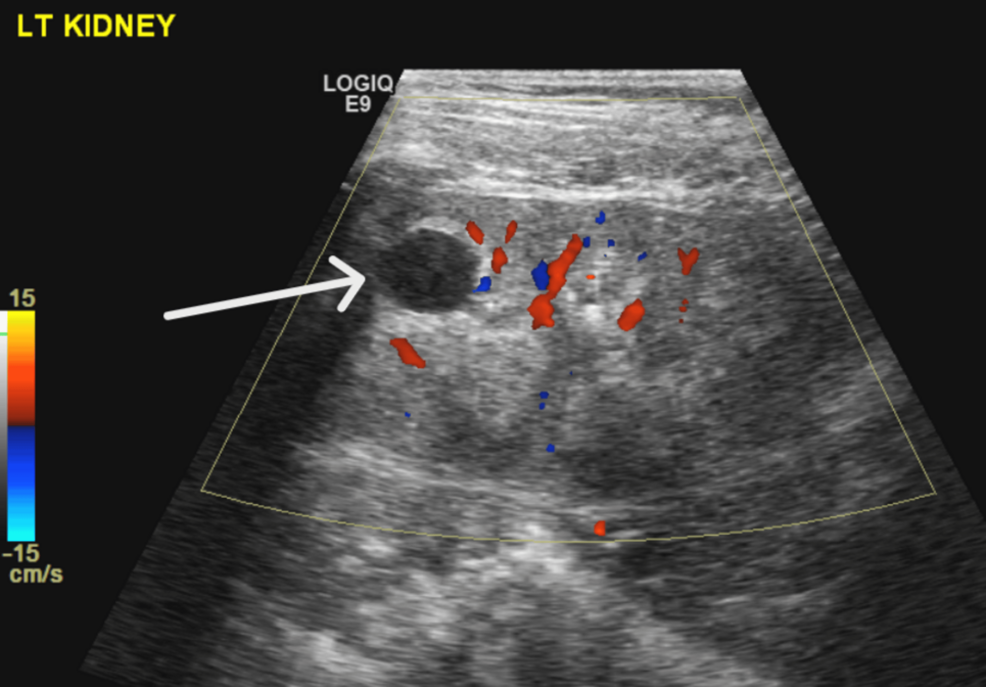

Cystic Kidney Disease: In some cases, kidney cysts may develop, contributing to renal dysfunction.

Early detection of these renal abnormalities is crucial. Regular monitoring of kidney function through urine analysis and blood tests (including creatinine and electrolytes) is essential for timely intervention. Chronic Kidney Disease (CKD) can develop if the condition is left unmanaged.